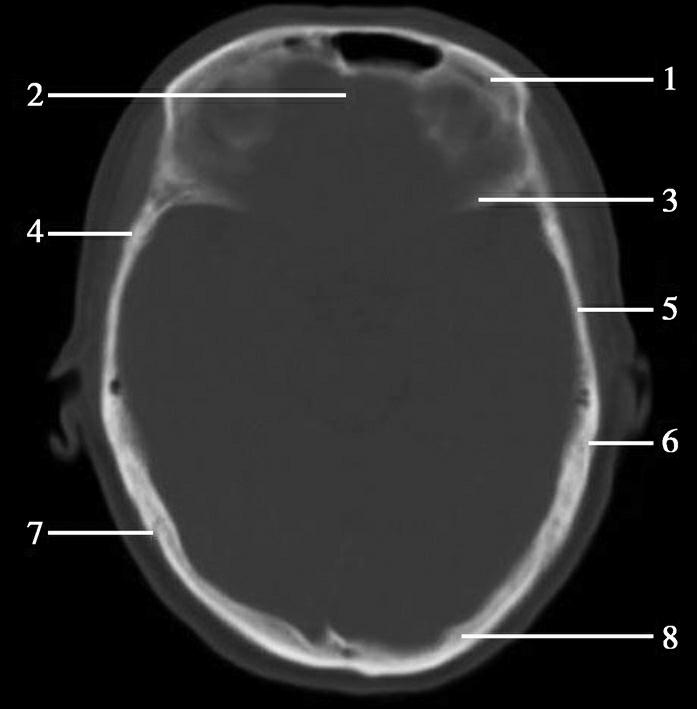

图1-2-2 颅底层面(骨窗)

A.横断面;B.横断面标注

1.鼻骨;2.筛窦纸板;3.颧骨眶突;4.翼腭窝;5.蝶骨大翼;6.卵圆孔;7.破裂孔;8.颞骨颧突;9.棘孔;10.斜坡;11.颞骨岩部;12.乳突;13.颈静脉孔;14.枕乳突缝;15.枕骨;16.枕内隆凸

层面前部呈开口向前的“V”字形,正中为鼻中隔,向两侧依次为筛窦和眼眶,眼眶内前部为眼球,后部为眶脂体。翼腭窝位于眼眶后部,窝内含有脂肪并有上颌神经通过。层面中部为蝶骨体,蝶骨体中部可见含气蝶窦,蝶窦后方为枕骨基底部,两者呈前后关系,其上面构成斜坡。蝶窦两侧为蝶骨大翼,其后外侧缘处由前向后可见卵圆孔和棘孔,分别有下颌神经和脑膜中动脉通过。斜坡外侧、岩骨尖前方为破裂孔。蝶骨大翼与眶外侧壁的颧骨借颧弓相连,颧弓和蝶骨大翼之间有咬肌及颞肌。层面中部外侧为外耳道。颞骨岩部呈“八”字形,相互之间借破裂孔软骨、蝶岩软骨结合和岩枕软骨结合连接。岩部后外侧的乳突部内可见乳突小房,乳突部与枕骨相接。岩骨后部可见颈静脉孔,内有颈内静脉、舌咽神经、迷走神经和副神经通过。层面后部为颅后窝,其内可见延髓,延髓前方为延髓前池,内有椎动脉,后外侧为小脑半球下部,后方为第四脑室、小脑扁桃体及小脑蚓部。

破裂孔、卵圆孔、棘孔及斜坡等均为重要的解剖结构,临床常见疾病如鼻咽癌常侵犯上述结构(图1-2-3)。颈静脉孔区较常见的肿瘤为颈静脉球瘤,常伴有颈静脉孔及其邻近骨质的破坏(图1-2-4)。